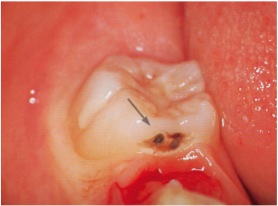

さらに、6歳臼歯で多いのが、写真のような歯と歯の間にできたムシ歯。

乳歯が抜けるとハッキリ解りますし、抜けてすぐに処置すれば、歯を削る量は最小限に止められます。

予防処置だけでなく、早期発見早期治療も、普段のマメな通院があってこそなのです。